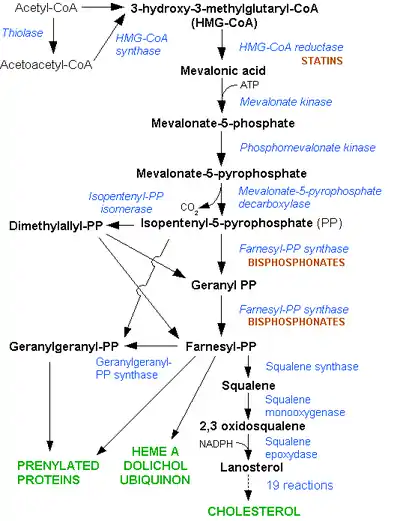

Terpenes and isoprenoids, including the carotenoids, are made by the assembly and modification of isoprene units donated from the reactive precursors isopentenyl pyrophosphate and dimethylallyl pyrophosphate. These precursors can be made in different ways. In animals and archaea, the mevalonate pathway produces these compounds from acetyl-CoA, while in plants and bacteria the non-mevalonate pathway uses pyruvate and glyceraldehyde 3-phosphate as substrates. One important reaction that uses these activated isoprene donors is steroid biosynthesis. Here, the isoprene units are joined together to make squalene and then folded up and formed into a set of rings to make lanosterol. Lanosterol can then be converted into other steroids such as cholesterol and ergosterol[1].

Steroid biosynthesis is an anabolic metabolic pathway that produces steroids from simple precursors. This pathway is carried out in different ways in animals than in many other organisms, making the pathway a common target for antibiotics and other anti-infective drugs. In addition, steroid metabolism in humans is the target of cholesterol-lowering drugs such as statins. It starts in the mevalonate pathway in humans, with Acetyl-CoA as building blocks, which form DMAPP and IPP. In following steps, DMAPP and IPP form lanosterol, the first steroid. Further modification belongs to the succeeding steroidogenesis. Steroidogenesis is the biological process by which steroids are generated from cholesterol and transformed into other steroids. The pathways of steroidogenesis differ between different species, but the pathways of human steroidogenesis are shown in the figure. Products of steroidogenesis include: androgens testosterone estrogens and progesterone corticoids cortisol aldosterone

All animal cells manufacture cholesterol with relative production rates varying by cell type and organ function. About 20–25% of total daily cholesterol production occurs in the liver; other sites of higher synthesis rates include the intestines, adrenal glands, and reproductive organs. Synthesis within the body starts with one molecule of acetyl CoA and one molecule of acetoacetyl-CoA, which are dehydrated to form 3-hydroxy-3-methylglutaryl CoA (HMG-CoA). This molecule is then reduced to mevalonate by the enzyme HMG-CoA reductase. This step is the regulated, rate-limiting and irreversible step in cholesterol synthesis and is the site of action for the statin drugs (HMG-CoA reductase competitive inhibitors). Mevalonate is then converted to 3-isopentenyl pyrophosphate in three reactions that require ATP. This molecule is decarboxylated to isopentenyl pyrophosphate, which is a key metabolite for various biological reactions. Three molecules of isopentenyl pyrophosphate condense to form farnesyl pyrophosphate through the action of geranyl transferase. Two molecules of farnesyl pyrophosphate then condense to form squalene by the action of squalene synthase in the endoplasmic reticulum. Oxidosqualene cyclase then cyclizes squalene to form lanosterol. Finally, lanosterol is then converted to cholesterol. Konrad Bloch and Feodor Lynen shared the Nobel Prize in Physiology or Medicine in 1964 for their discoveries concerning the mechanism and regulation of cholesterol and fatty acid metabolism[4].

Mevalonic acid pathway Many organisms manufacture terpenoids through the HMG-CoA reductase pathway, the pathway that also produces cholesterol. The reactions take place in the cytosol. The pathway was discovered in the 1950s.

Mevalonate pathway and Statins

The mevalonate pathway or HMG-CoA reductase pathway or mevalonate-dependent (MAD) route or isoprenoid pathway, is an important cellular metabolic pathway present in all higher eukaryotes and many bacteria. It is important for the production of dimethylallyl pyrophosphate (DMAPP) and isopentenyl pyrophosphate (IPP), which serve as the basis for the biosynthesis of molecules used in processes as diverse as terpenoid synthesis, protein prenylation, cell membrane maintenance, hormones, protein anchoring, and N-glycosylation. It is also a part of steroid biosynthesis[24].

Several key enzymes can be activated through DNA transcription al regulation on activation of SREBP (sterol regulatory element-binding protein-1 and -2). This intracellular sensor detects low cholesterol levels and stimulates endogenous production by the HMG-CoA reductase pathway, as well as increasing lipoprotein uptake by up-regulating the LDL-receptor. Regulation of this pathway is also achieved by controlling the rate of translation of the mRNA, degradation of reductase and phosphorylation.

In 1971, Akira Endo, a Japanese biochemist working for the drug company Sankyo, began the search for a cholesterol-lowering drug. Research had already shown that cholesterol is mostly manufactured by the body in the liver, using an enzyme known as HMG-CoA reductase. Endo and his team reasoned that certain microorganisms may produce inhibitors of the enzyme to defend themselves against other organisms, as mevalonate is a precursor of many substances required by organisms for the maintenance of their cell wall (ergosterol) or cytoskeleton (isoprenoids). The first agent they identified was mevastatin (ML-236B), a molecule produced by the fungus Penicillium citrinum. Journalist John Simons writes in Fortune magazine that word of the discovery spread quickly through the medical community, as did rumors linking the statin to tumors, muscle deterioration, and sometimes death in laboratory dogs. Several drug companies were put off by these reports, but P. Roy Vagelos, the chief scientist and later CEO of Merck & Co, showed an interest, and made several trips to Japan starting in 1975. By 1978, Merck had isolated lovastatin (mevinolin, MK803) from the fungus Aspergillus terreus, first marketed in 1987 as Mevacor. A link between cholesterol and cardiovascular disease, known as the lipid hypothesis, had already been suggested. Cholesterol is the main constituent of atheroma, the fatty lumps in the wall of arteries that occur in atherosclerosis and, when ruptured, cause the vast majority of heart attacks. Treatment consisted mainly of dietary measures such as a low-fat diet, and poorly tolerated medicines such as clofibrate, cholestyramine and nicotinic acid. Cholesterol researcher Daniel Steinberg writes that while the Coronary Primary Prevention Trial of 1984 demonstrated that cholesterol lowering could significantly reduce the risk of heart attacks and angina, physicians, including cardiologists, remained largely unconvinced. To market statins effectively, Merck had to convince the public about the dangers of high cholesterol, and doctors that statins were safe and would extend lives. As a result of public campaigns, people became familiar with their cholesterol numbers and the difference between "good" and "bad" cholesterol, and rival pharmaceutical companies began producing their own statins, such as pravastatin (Pravachol), manufactured by Sankyo and Bristol-Myers Squibb. In April 1994, the results of a Merck-sponsored study, the Scandinavian Simvastatin Survival Study or "4S", were announced. Researchers tested simvastatin, later sold by Merck as Zocor, on 4,444 patients with high cholesterol and heart disease. After five years, the study concluded that patients saw a 35-percent reduction in their cholesterol, and their chances of dying of a heart attack were reduced by 42 percent. In 1995, Zocor and Mevacor both made Merck over US$1 billion. Endo was awarded the 2006 Japan Prize, and the Lasker-DeBakey Clinical Medical Research Award in 2008. Statins act by competitively inhibiting HMG-CoA reductase, the first committed enzyme of the HMG-CoA reductase pathway. Because statins are similar to HMG-CoA on a molecular level they take the place of HMG-CoA in the enzyme and reduce the rate by which it is able to produce mevalonate, the next molecule in the cascade that eventually produces cholesterol, as well as a number of other compounds. This ultimately reduces cholesterol via several mechanisms[25].

Mode of action of Statins

Inhibiting cholesterol synthesis By inhibiting HMG-CoA reductase, statins block the pathway for synthesizing cholesterol in the liver. This is significant because most circulating cholesterol comes from internal manufacture rather than the diet. When the liver can no longer produce cholesterol, levels of cholesterol in the blood will fall. Cholesterol synthesis appears to occur mostly at night, so statins with short half-lives are usually taken at night to maximize their effect. Studies have shown greater LDL and total cholesterol reductions in the short-acting simvastatin taken at night rather than the morning, but have shown no difference in the long-acting atorvastatin.

Increasing LDL uptake Liver cells sense the reduced levels of liver cholesterol and seek to compensate by synthesizing LDL receptors to draw cholesterol out of the circulation. This is accomplished via protease enzymes that cleave a protein called "membrane-bound sterol regulatory element binding protein", which migrates to the nucleus and causes increased production of various other proteins and enzymes, including the LDL receptor. The LDL receptor then relocates to the liver cell membrane and binds to passing LDL and VLDL particles (the "bad cholesterol" linked to disease). LDL and VLDL are drawn out of circulation into the liver where the cholesterol is reprocessed into bile salts. These are excreted, and subsequently recycled mostly by an internal bile salt circulation.

Other effects Statins exhibit action beyond lipid-lowering activity in the prevention of atherosclerosis. The ASTEROID trial showed direct ultrasound evidence of atheroma regression during statin therapy. Researchers hypothesize that statins prevent cardiovascular disease via four proposed mechanisms (all subjects of a large body of biomedical research): Improve endothelial function, Modulate inflammatory responses, Maintain plaque stability, Prevent thrombus formation, Statins may even benefit those without high cholesterol. In 2008 the JUPITER study showed fewer stroke, heart attacks, and surgeries even for patients who had no history of high cholesterol or heart disease, but only elevated C-reactive protein levels. There were also 20% fewer deaths (mainly from reduction in cancer deaths) though deaths from cardiovascular causes were not reduced